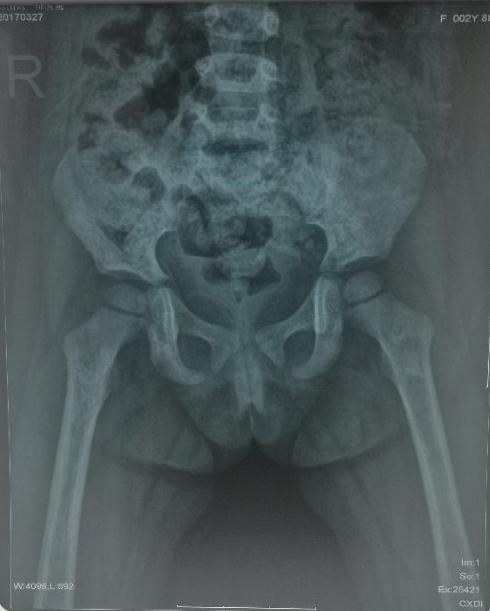

那一天,一张照片传到了麻醉大家庭的微信群,这是一个2岁孩子的髋关节X光片,之后又是一张孩子和妈妈的合影。

这是麻醉科辛维政主任从新疆阿克苏发回来的照片。辛主任在那里挂职锻炼,照片中的孩子是他认亲结对的新疆当地老乡。辛主任说孩子走路时双侧髋部疼痛,左侧为重,当地医疗条件有限,建议远程会诊。科室立刻找骨科郑稼主任会诊,初步诊断为反应性滑膜炎,建议进一步检查。第二张照片让大家震惊,孩子穿着有破损边缘的旧秋裤。辛主任说,这个家庭很贫穷,虽然孩子的父母努力劳作,仍然无法改变现状。孟凡民主任看过深思片刻,说,“我们要帮帮他们,在科室发起募捐倡议”。辛主任看到募捐倡议,也很激动,补充说考虑到民族和宗教信仰,建议只收新的物品。孟主任带头捐款,科室人员积极响应。远赴异国度蜜月的麻醉护士吴静华,一下飞机看到倡议书,立刻捐来善款;钱建华主任不仅捐款,发现家中有孙子的新书包未用时,立刻捐了出来。在有限的时间内共筹得善款1万余元和两个新书包。